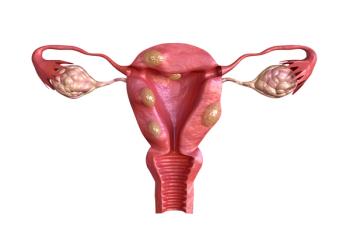

“Over 70% of women are estimated to develop uterine fibroids by age 50,” said senior author Irene Aninye, PhD, chief science officer for the Society for Women’s Health Research (SWHR) in Washington, D.C. “Fibroids are a complex condition that can range from being asymptomatic to having deleterious effects on a woman’s health and quality of life.”

Many of the glaring disparities that exist in care for the 26 million women in the United States who suffer from uterine fibroids, which disproportionately affects up to 80% of Black women, are being aggressively addressed though a new multifaceted campaign called UNmuting Fibroids.

Due to uterine fibroids being a potential cause of infertility, treatment options like myomectomy should be discussed individually with the patient, according to an article published in Diagnostics that evaluated the relationship.